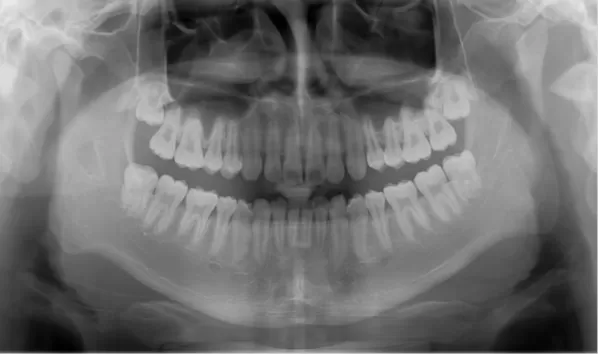

Rayons X avant le traitement

[Radiographie panoramique/Céphalogramme latéral]